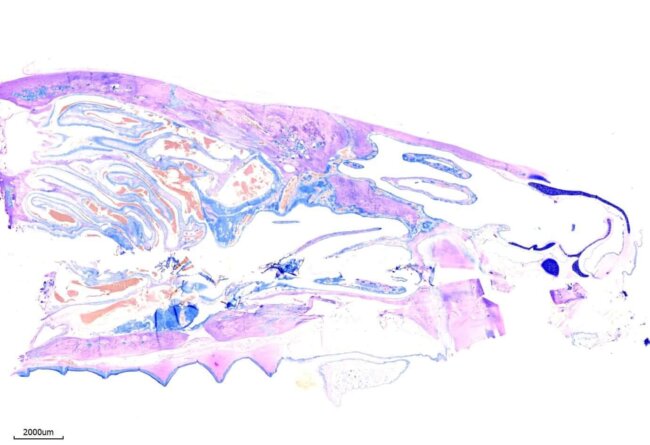

Giemsa stain for FFPE (formalin-fixed paraffin-embedded) sections 難得少見的鼠頭顱切片技術 最新消息, 立眾病理By 立众小編1號2021-07-21